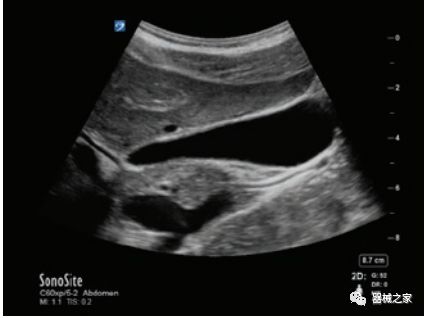

GE Healthcare用于胎儿超声的胎儿心脏和血管分析软件,在Voluson E10上提供,有助于在不到三分钟的时间内评估胎儿的心脏形状,大小和收缩性。称为辐射流的功能以三维视图显示血流。它还可以帮助显示缓慢流动的血液,例如神经血管循环。

Voluson E10